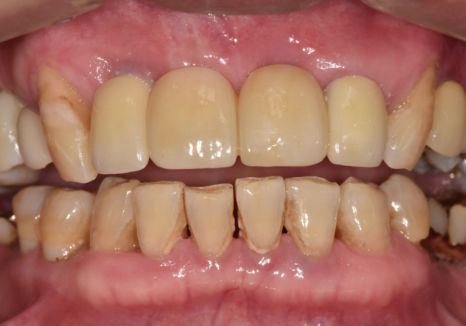

이번 환자분은 앞니가 많이 흔들렸습니다.

잇몸도 계속 부었다 가라앉았다를

반복하셨다고 합니다.

앞니가 너무 흔들리다 보니,

흔들리는 앞니 3개를

왼쪽 송곳니에 철사로

연결(스플린트) 해서 생활하고 계셨어요.

250106 스플린트로 묶인 치아

잠깐은 버틸 수 있지만,

근본 문제가 해결된 건 아니죠.

즉, 이 환자분은

"조금 흔들리는 수준"이 아니라

더 이상 미루기 어려운 수준의

흔들림이 있었다는 뜻입니다.

하지만, 방사선 사진과 입안을 살펴보니,

오른쪽 작은 어금니(#15) : 발치로 인해 치아 상실된 상태, 뼈가 다량 녹은 상태

앞니 3개 (#11,21,22) : 복합 치주염으로 뼈가 녹아 잇몸 상태가 좋지 않고 흔들림이 심함

만약, 보장을 위해 1년 더 기다리게 된다면

앞니 쪽은 더 흔들리고

잇몸이 더 내려갈 가능성이 컸습니다.